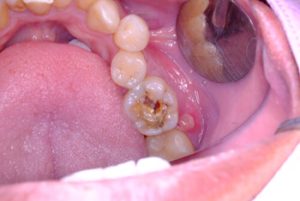

3. Dentine involvement: sensitivity and darker lesions.

4. Deeper layers invasion: bacteria reach the tooth pulp, causing inflammation.

5. Abscess and structural collapse: risk of extraction or root canals.

Can Tooth Decay Spread problemWhile decay can be silent for months, certain early signs hint that damage is underway:

• Occasional tooth sensitivity to cold drinks.

• Dark shadows on a tooth’s enamel.

• Rough patches you can feel with your tongue.

• Food gets caught between teeth or on a pitted surface.

• Bad taste that persists even after brushing.

Any of these clues signal that a tooth cavity may be forming and that it’s time for early treatment.